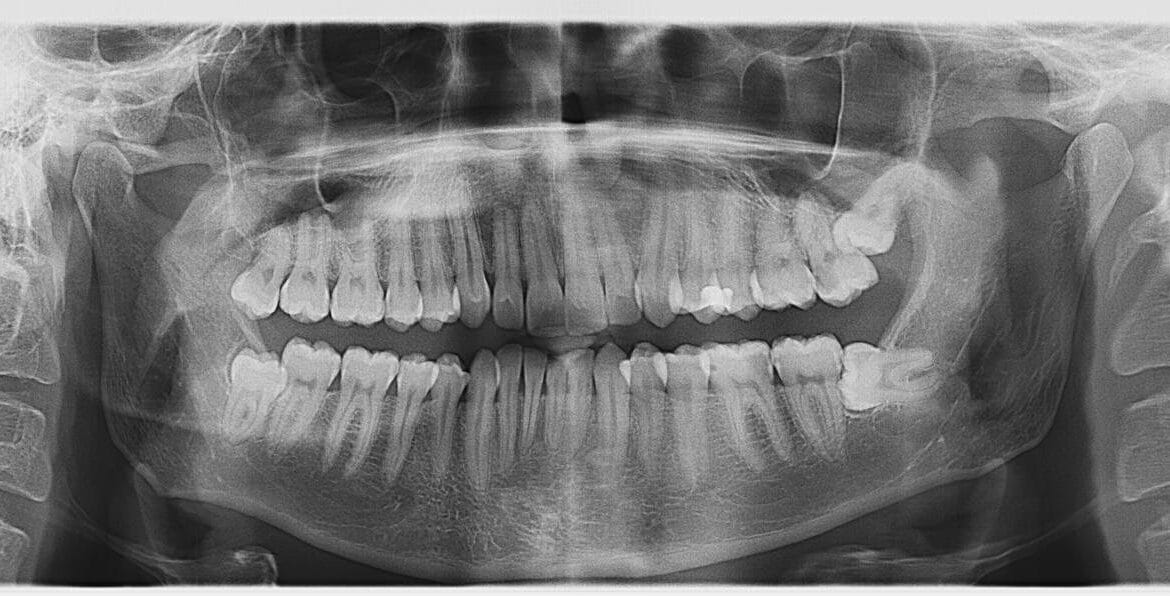

КТ зубів та 3D сканування в клініці Dentistman у Києві

У сучасній стоматології точна діагностика є основою успішного лікування. Клініка Dentistman пропонує передові послуги комп'ютерної томографії (КТ) зубів та 3D-сканування, які дозволяють отримати максимально детальні зображення зубів, щелеп, суглобів та навколишніх тканин. Ці технології незамінні при плануванні дентальної імплантації, ортодонтичного лікування, ендодонтії, видалення зубів мудрості та складних хірургічних втручань. Що...